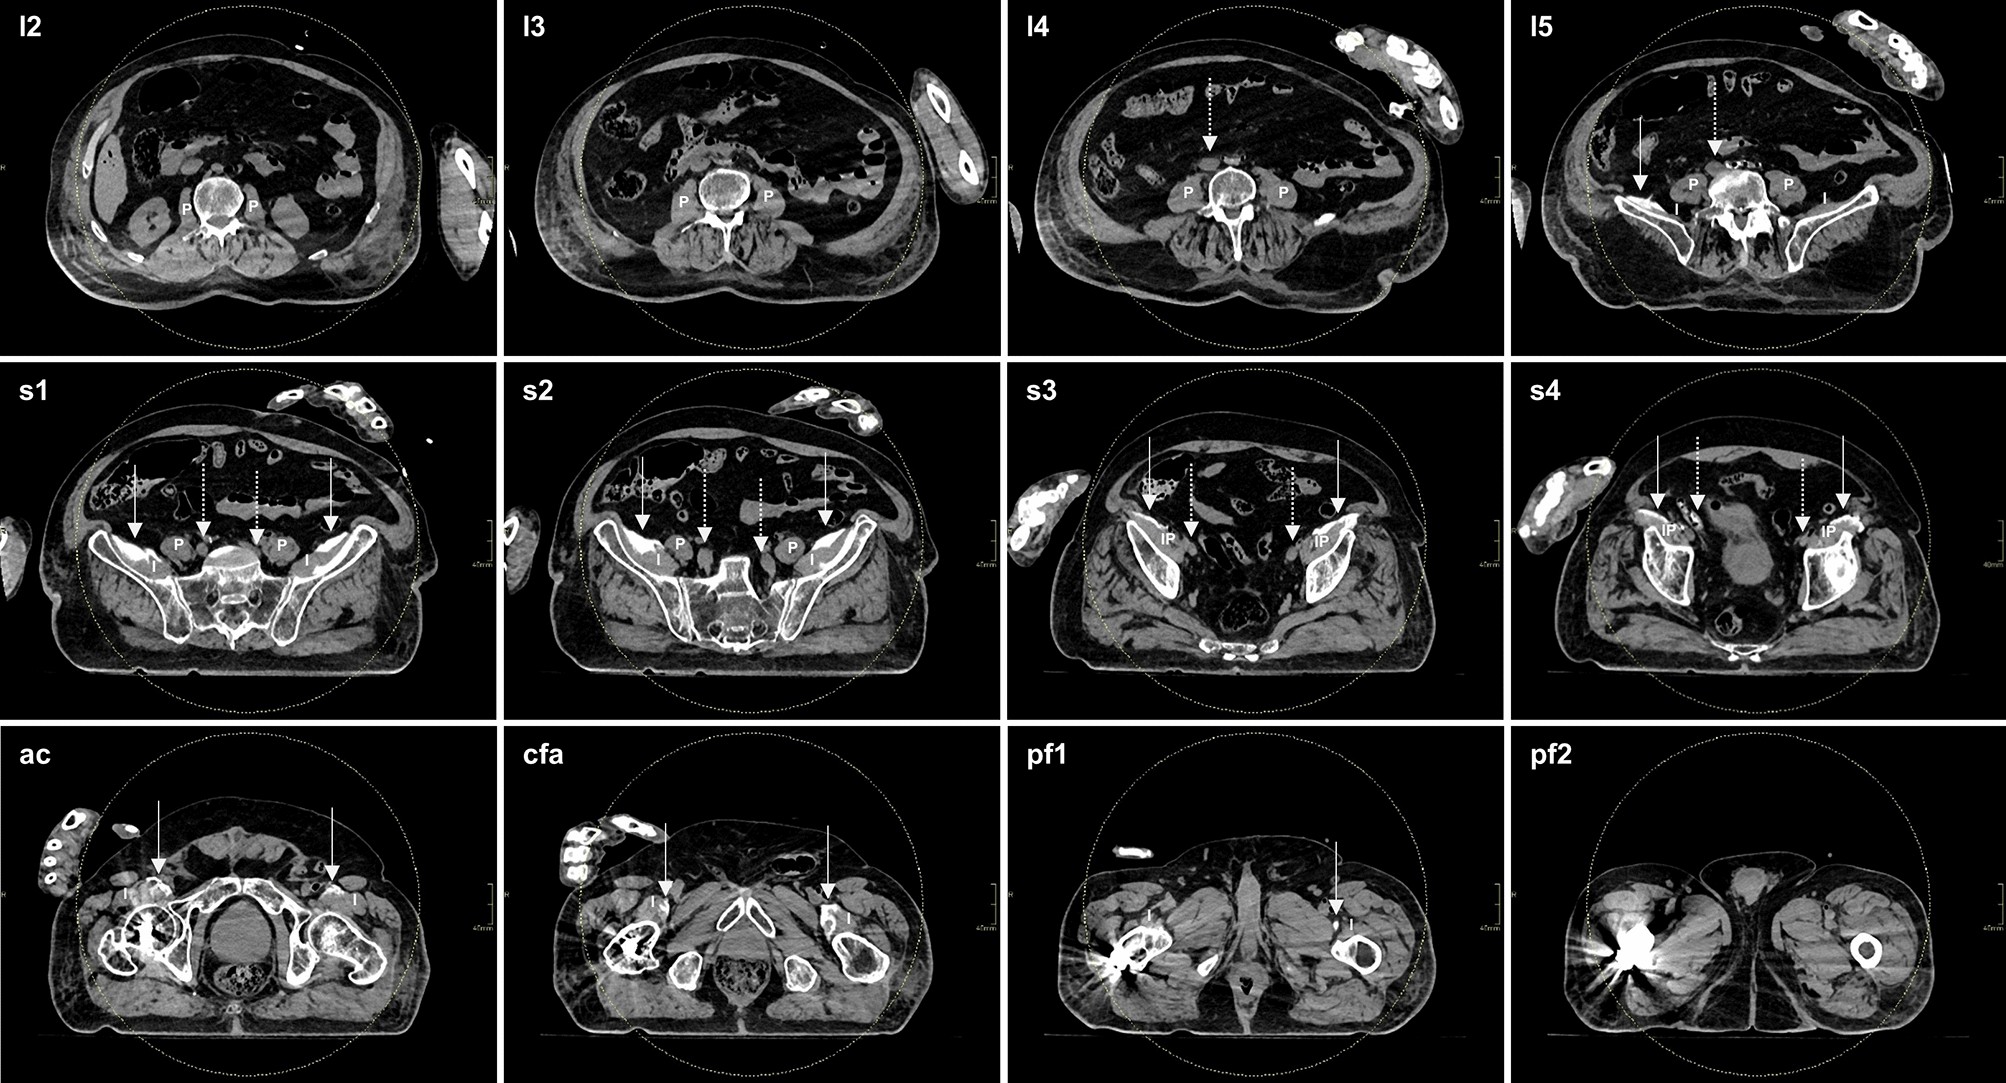

Figure 3

Axial CT slices detailing typical spread of injectate after (bilateral) S-FICB-H. The LA-based contrast mixture was determined to reach a maximum height corresponding to the fifth lumbar vertebra on the left side and the intervertebral disc of lumbar vertebrae four-five on the right side. Medial spread of contrast stayed anterior to the iliopsoas muscles and iliac arteries. As such, contrast remained removed of the location of the lumbar plexus and ON, both in the cranial and medial directions. Dotted arrows point to the iliac arteries, solid arrows point to the contrast. l lumbar vertebra, s sacral vertebra, ac acetabulum, cfa common femoral artery, pf proximal femur, P psoas muscle, I iliacus muscle, IP iliopsoas muscle.